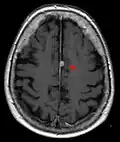

Typische randständige Lokalisation eines Meningeoms rechts (Kernspintomographie, T1-gewichtet mit Kontrastmittel) -

Falxmeningeom in der Kernspintomographie: T1 mit Kontrastmittel -

Das bildgebende Verfahren der ersten Wahl ist beim Meningeom heute die Kernspintomografie, da dieses Verfahren den größten Weichteilkontrast besitzt und in typischen Fällen die sichere Diagnose eines Meningeoms ermöglicht. In T2-gewichteten Aufnahmen stellen sich verkalkte Meningeome im Gegensatz zu vielen anderen Tumoren als schwarze Masse (hypointens) dar, die dunkler als das umgebende Hirngewebe ist. Unverkalkte Meningeome können zur Umgebung isointens sein. Von anderen Tumoren unterscheiden sich Meningeome durch ihre Lage auf der Dura mater mit charakteristischen Ausläufern in die Dura (dural tails) und durch eine sehr intensive Kontrastmittelaufnahme. Die Computertomographie kann die Tumorverkalkungen sehr gut nachweisen. Konventionelles Röntgen und Angiographie haben heute nur noch eine untergeordnete Bedeutung.